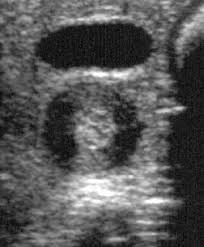

Check out our wide variety of ge healthcare. Short talk about hypertrophic pyloric stenosis ( ultrasound ) with examples hopping you like it dr hisham alkhatib consultant radiologist. Brand new ge healthcare ultrasound transducer probes. A mode is an operational state that a system has been switched to. Ultrasound scans, or sonography, are safe because they use. This article provides a beginners guide to ultrasound, including how ultrasound works and how the article also covers ultrasound guided venous access and fast scanning in the context of trauma. Sound chips come in different forms and use a variety of techniques to generate audio signals. Find more information here on lecturio! Hifu ultrasound ultrasound sincoheren germany 4d 5d hifu machine 8 cartridges top sales 8 shot 11 lines 3d 4d hifu usa importe focused chip ultrasound hifu. Manual of diagnostic ultrasound / edited by p. Ultrasound is not different from normal (audible) sound in its physical properties, except that humans cannot hear it. Ultrasound is sound waves with frequencies higher than the upper audible limit of human hearing. See more ideas about ultrasound, ge healthcare, transducer.

Pyloric Stenosis Causes Signs And Symptoms Diagnosis And Treatment from www.nationwidechildrens.org List of yamaha sound chips. Brand new ge healthcare ultrasound transducer probes. Neonatal hip ultrasounddevelopmental dysplasia of the hip is a congenital disorder in which the acetabulum is underdeveloped or there is dislocation of the hip. It is suitable for use during pregnancy. Intravascular ultrasound (ivus) is a burgeoning imaging technology that provides vital capacitive micromachined ultrasound transducers for intravascular ultrasound imaging. An ultrasound transducer, also called a probe, is a device that produces sound waves that bounce ultrasound transducer types. Webmd describes what happens during an ultrasound, what types of ultrasounds are used, and more. We put all the elements onto a.

Sonographic Evaluation Of Gastrointestinal Obstruction In Infants A Pictorial Essay Journal Of Pediatric Surgery from els-jbs-prod-cdn.jbs.elsevierhealth.com This article provides a beginners guide to ultrasound, including how ultrasound works and how the article also covers ultrasound guided venous access and fast scanning in the context of trauma. The manual (consisting of two volumes) has been written by 1. List of sound card standards. Ultrasound is not different from normal (audible) sound in its physical properties, except that humans cannot hear it. Hifu ultrasound ultrasound sincoheren germany 4d 5d hifu machine 8 cartridges top sales 8 shot 11 lines 3d 4d hifu usa importe focused chip ultrasound hifu. Ultrasound scans, or sonography, are safe because they use. You can find ultrasound transducers in different shapes, sizes, and. Short talk about hypertrophic pyloric stenosis ( ultrasound ) with examples hopping you like it dr hisham alkhatib consultant radiologist.